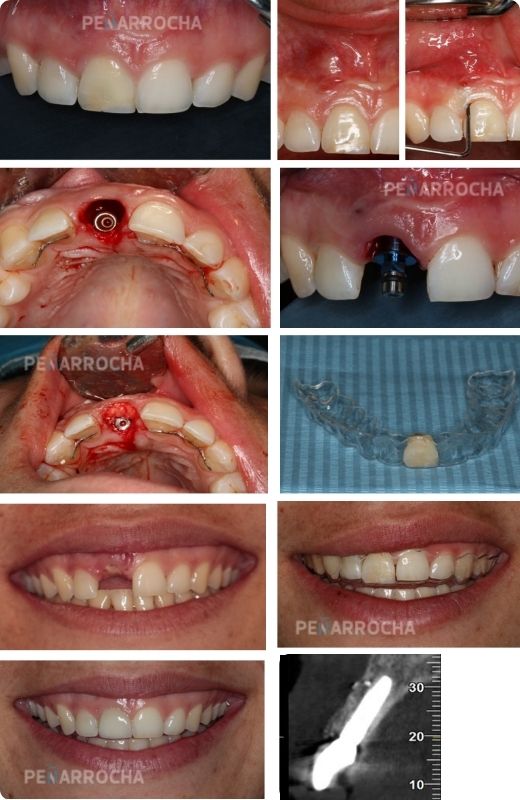

secuencia caso tratamiento implantes dentales inmediatos en valencia dres penarrocha cirugia e implantologia oral en valencia

¿Cómo se realiza el tratamiento de implantes dentales inmediatos?

El éxito de los implantes dentales inmediatos depende de un diagnóstico exhaustivo y una planificación personalizada.

En nuestra clínica de los Dres. Peñarrocha, seguimos un procedimiento riguroso para garantizar resultados estéticos y funcionales, siguiendo estos pasos:

1. Evaluación inicial y diagnóstico

En la primera consulta, realizamos un estudio completo mediante radiografías y tomografía 3D para valorar la cantidad y calidad del hueso disponible. Esto permite planificar el tratamiento con precisión.

2. Extracción del diente

Si el diente está dañado, se realiza su extracción cuidadosa para preservar al máximo los tejidos gingivales y óseos.

3. Colocación del implante

El implante de titanio se inserta inmediatamente en el alveolo del diente extraído. En algunos casos, se coloca una corona provisional fija para recuperar de forma inmediata la funcionalidad y la estética.

4. Osteointegración

El implante se fusiona con el hueso durante un período de 2 a 4 meses. Durante este tiempo, es fundamental seguir las pautas recomendadas por el dentista para asegurar la integración.

5. Colocación de la corona definitiva

Tras el período de osteointegración, se coloca una corona personalizada, diseñada para integrarse perfectamente con los demás dientes.